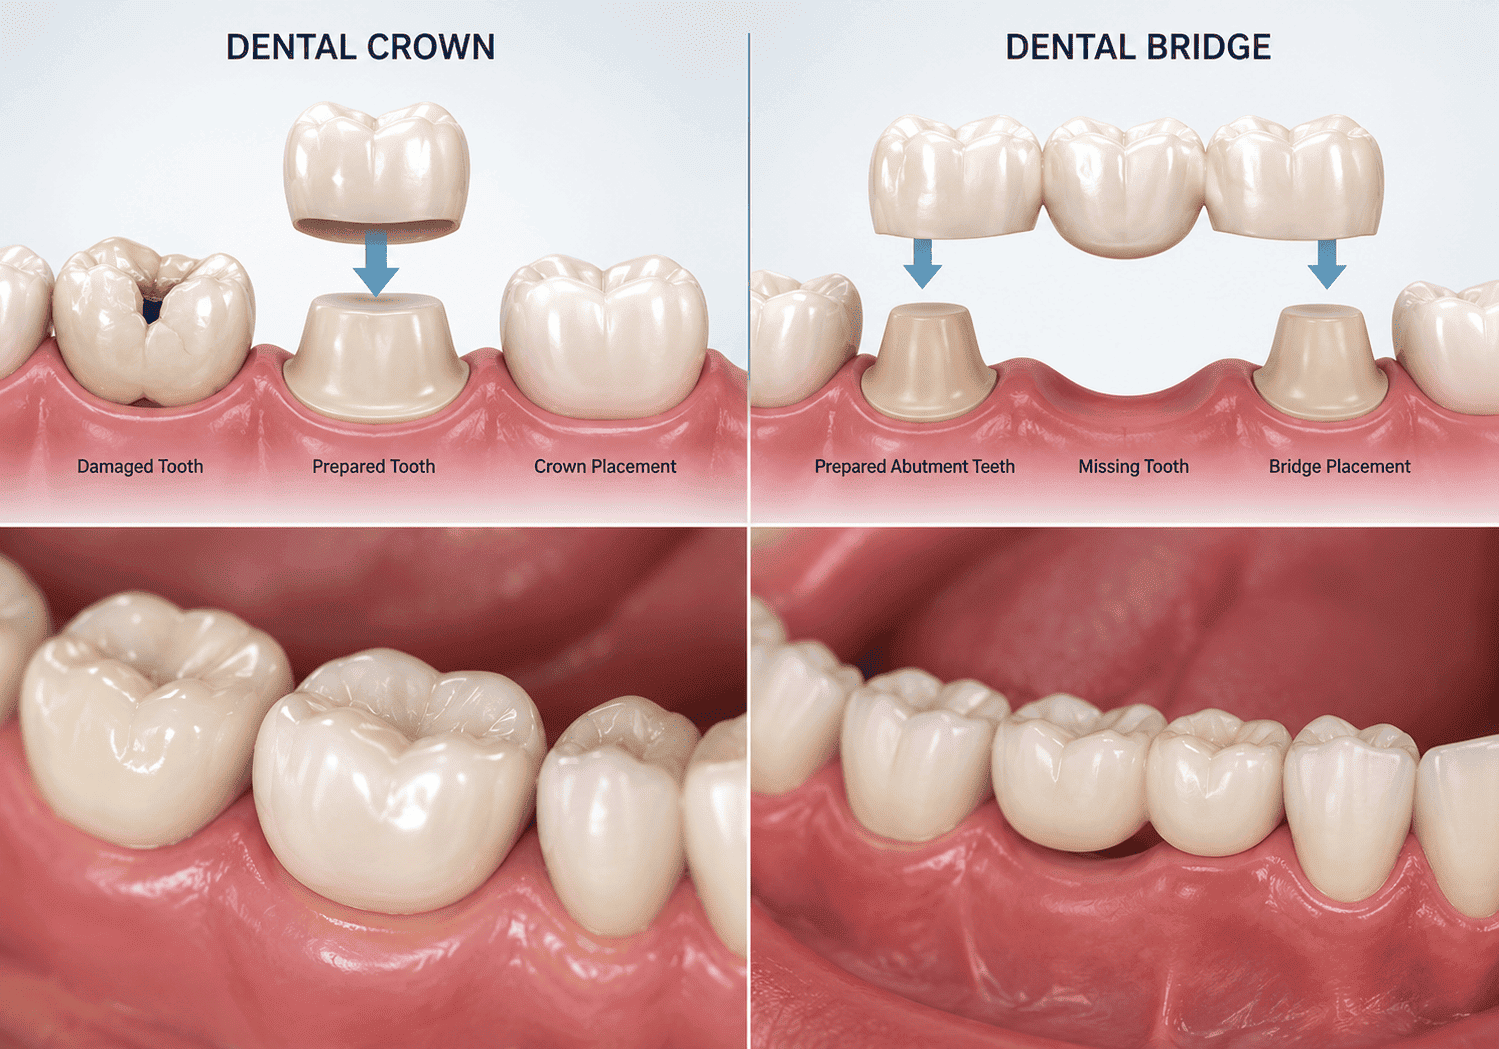

ক্রাউন ও ব্রিজ চিকিৎসা (Crown & Bridge)